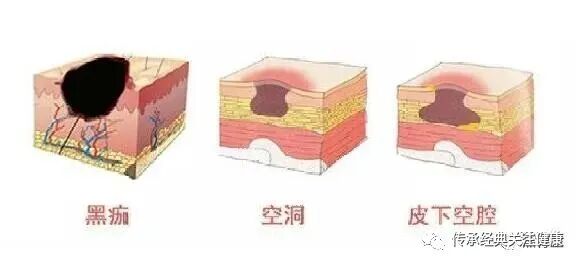

空洞型褥疮的典型特点是“外小内大”:疮口看起来很小,但皮下或深部组织已经形成了巨大的空腔,就像一个“暗洞”,因此得

名空洞型褥疮。这种褥疮的形成,大多与不当处理(尤其是盲目干燥、结痂)有关——疮口表面愈合,但其内部的创面和空腔

并未愈合,形成暗洞,导致坏死组织、脓液无法排出,持续侵蚀深部组织。

根据疮口与内部空腔的大小、深浅,空洞型褥疮可分为三种:一是普通空洞褥疮,疮口大小与内部空腔大小基本一致;二是皮

下空腔褥疮,疮口小但内部空腔较大;三是窦道型褥疮,疮口与内部空腔都较小,但深度极深。需要特别注意的是,这三种空

洞型褥疮的处置方法完全不同,必须根据创面具体情况针对性处理,切记盲目处理只会加重病情。

空洞型褥疮的处理核心的是---“完成空腔化腐”“打通引流、清除腐肉”——由于疮口较小,很难直接清理内部的坏死组织和脓液,

若处理不当,很容易出现“表面愈合、内部溃烂”的情况,*终导致褥疮向更深层发展,累及骨骼、引发骨髓炎。